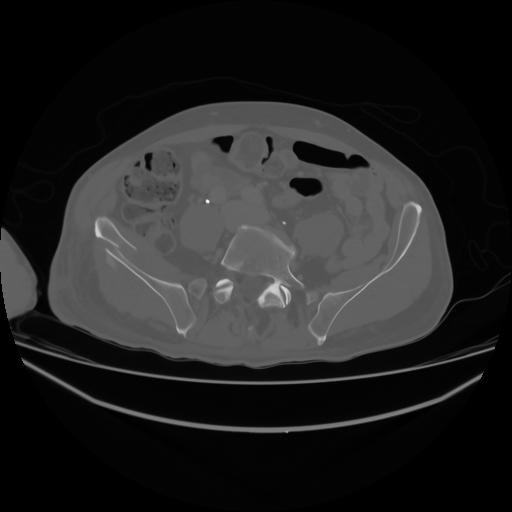

4 CUERPO,CE,Axial,3.0,CUERPO,,